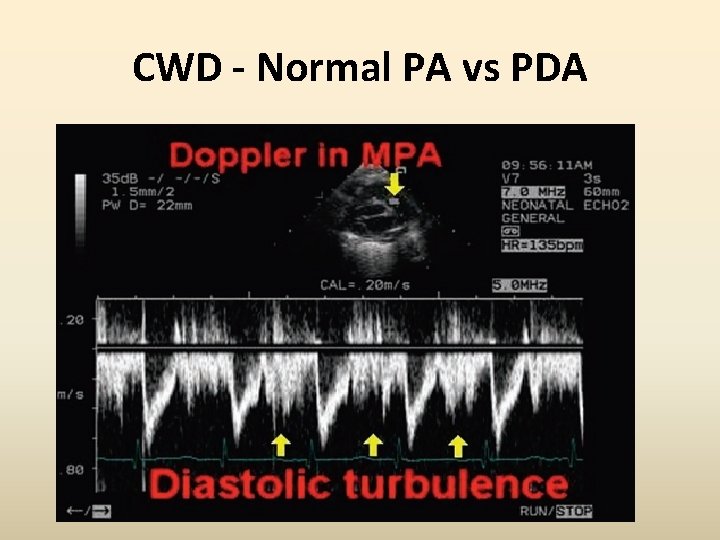

CWD - Normal PA vs PDA